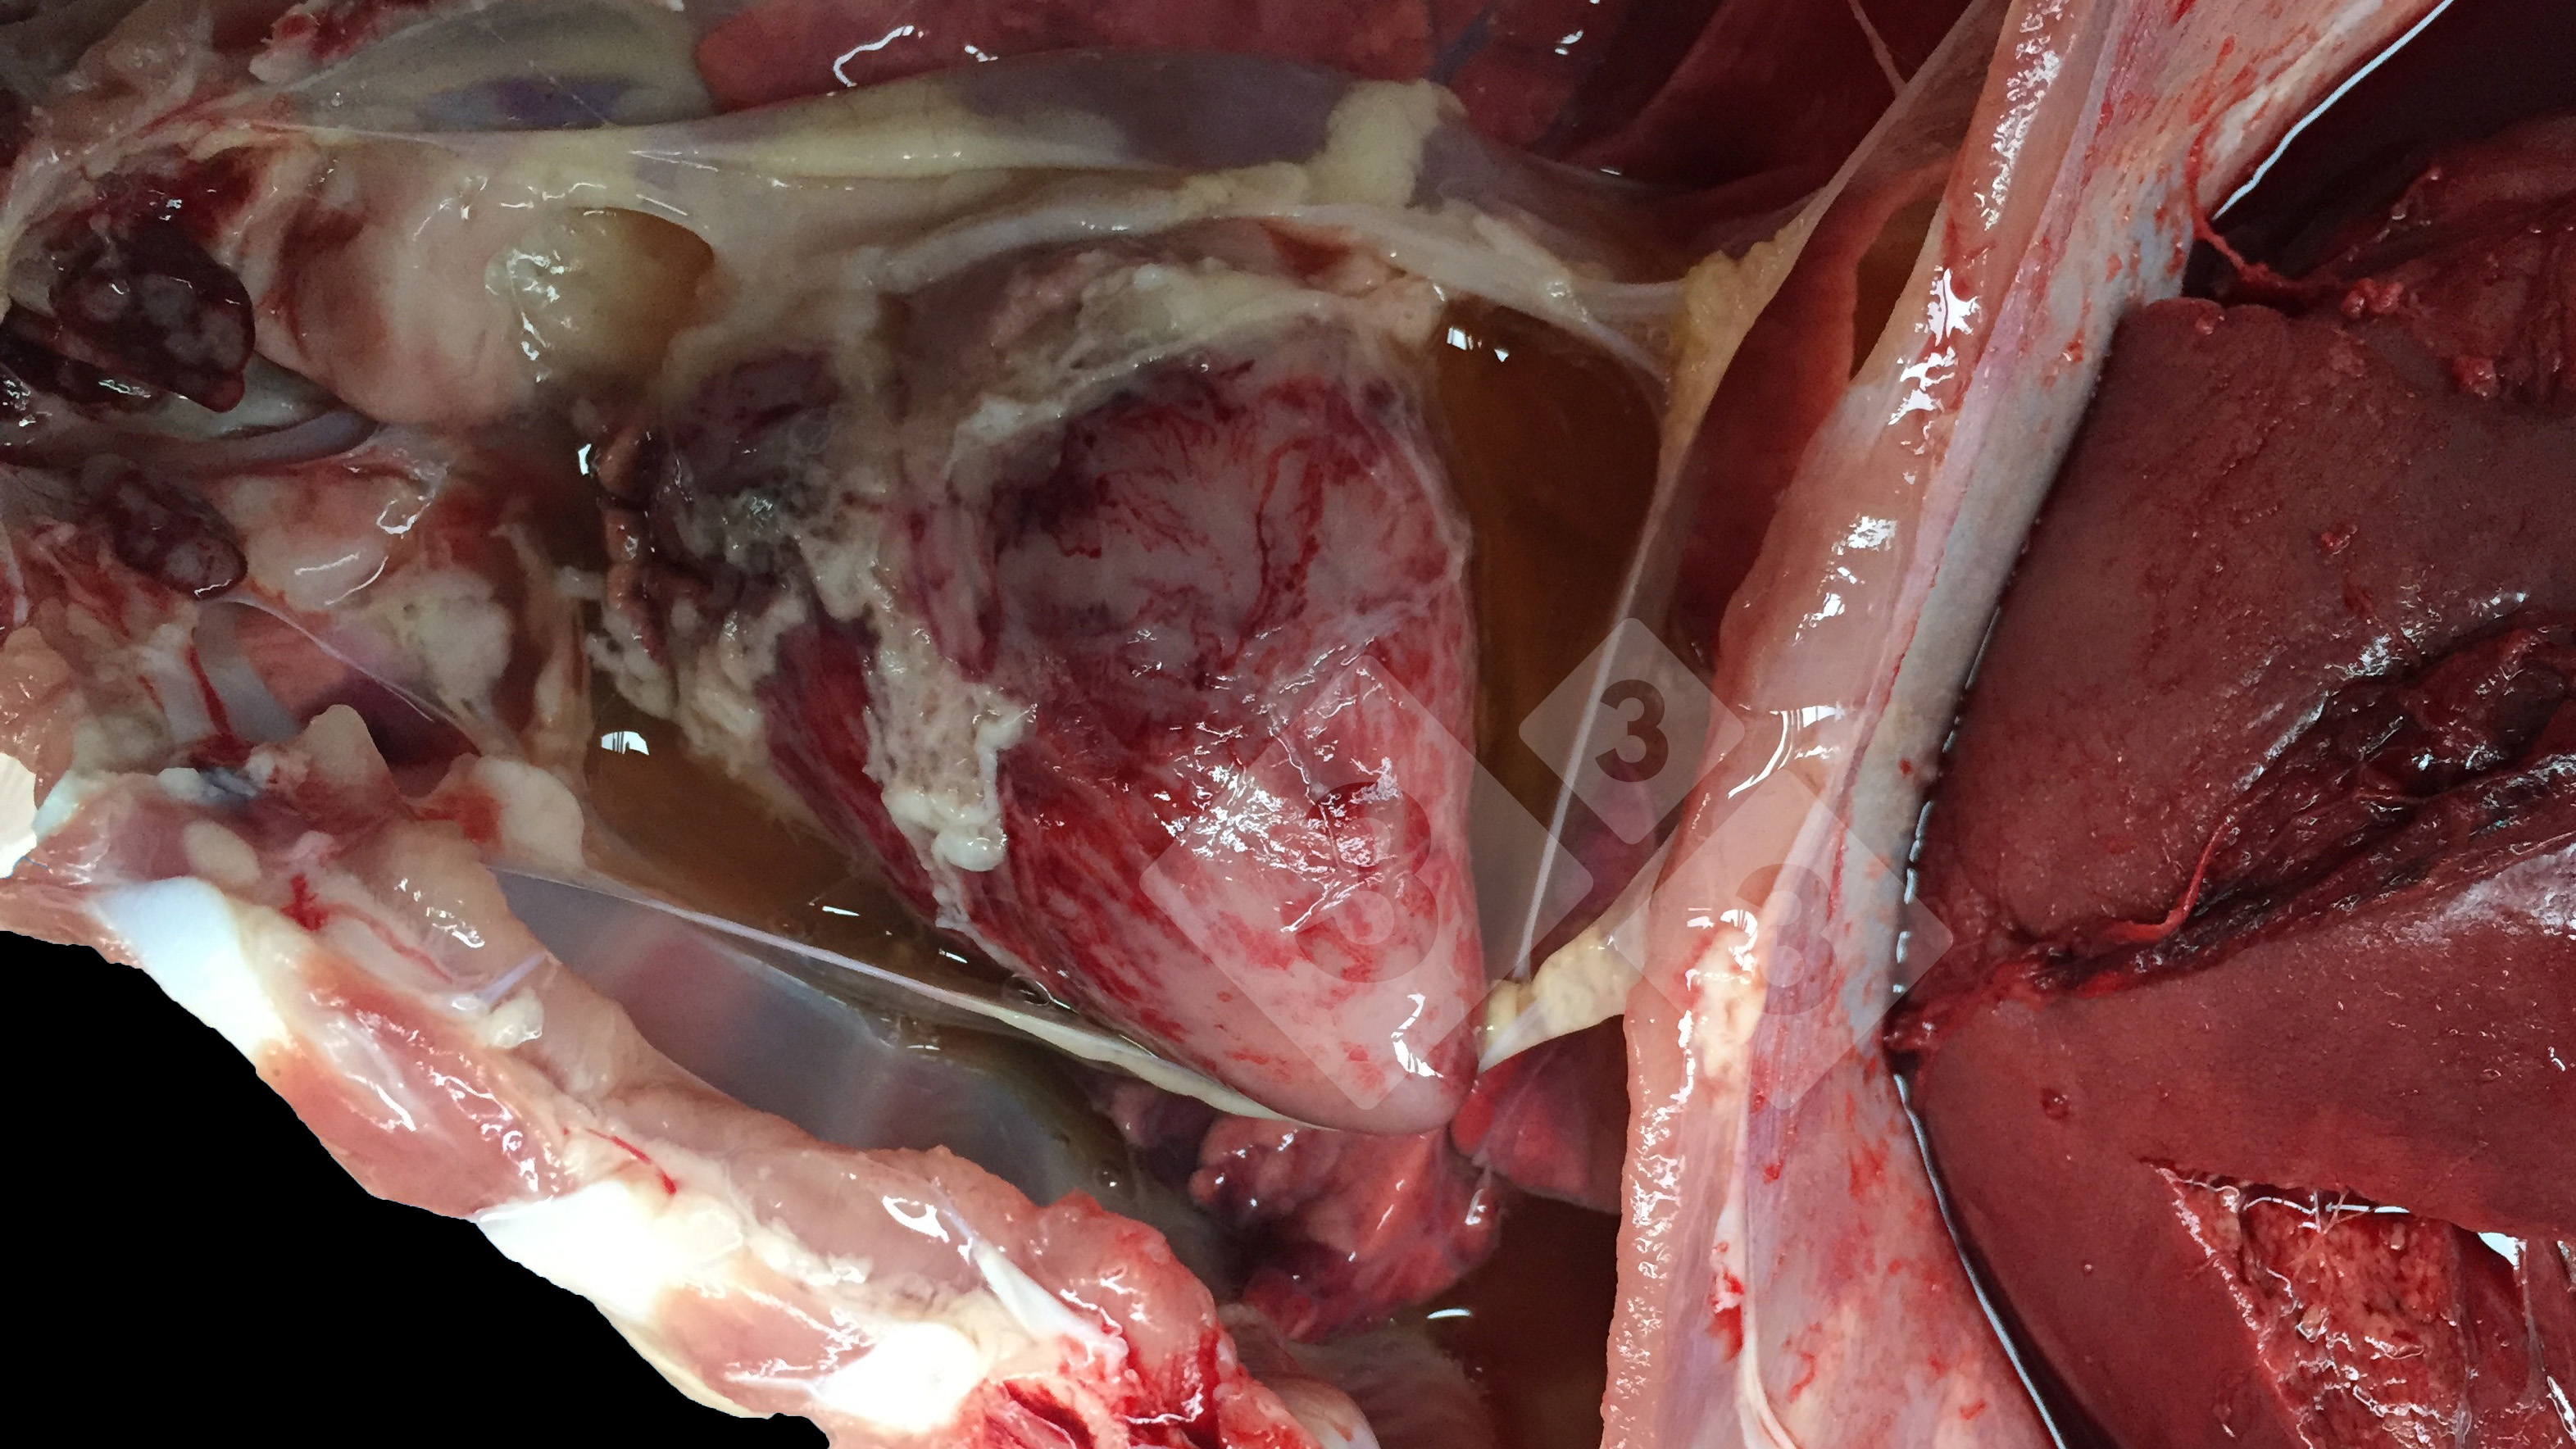

Mort subite chez des porcs de 6 à 8 semaines. Cadavres pâles, avec liquide abdominal hémorragique avec brins de sang coagulé et rupture hépatique. Excès de liquide dans le thorax. Coeur et muscles pâles. Quelle est la cause la plus probable?